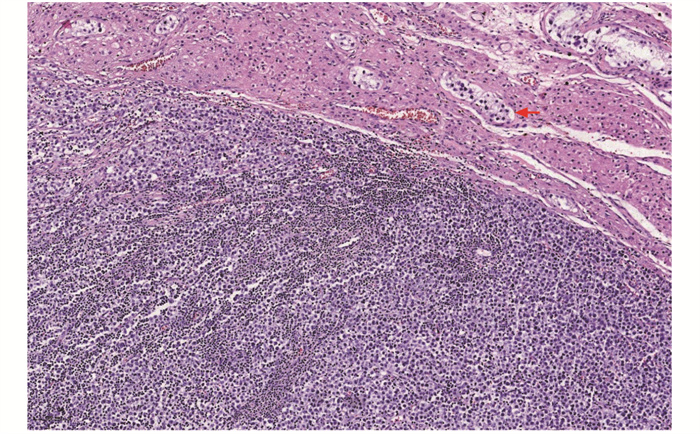

结果  共纳入睾丸和附件病变患者317例,平均年龄(38.72±19.74)岁,临床症状以阴囊区肿大、疼痛为主(88.01%, 279/317),肿瘤性疾病85例(26.81%,85/317)、非肿瘤性疾病232例(73.19%,232/317)。病变组织大体表现:肿瘤性疾病的病灶直径2~17 cm,呈结节或分叶状,切面为实性或囊实性,部分区域可见出血或坏死;非肿瘤性疾病的病灶直径0.6~8 cm,多呈囊性,囊壁较光滑,部分呈实性结节状。85例肿瘤性疾病患者中,平均年龄(38.09±14.52)岁,恶性肿瘤占比96.47%,肿瘤类型依次为生殖细胞肿瘤(88.24%,75/85)、淋巴造血系统肿瘤(4.71%,4/85)、间叶肿瘤(4.71%, 4/85)、间质细胞瘤(1.18%,1/85)、附睾乳头状囊腺瘤(1.18%,1/85),其中生殖细胞肿瘤中,主要为精原细胞瘤(66.67%,50/75),其次为混合性生殖细胞肿瘤(14.67%,11/75)、胚胎性癌(12.00%,9/75)。4例淋巴造血系统肿瘤均为弥漫性大B细胞淋巴瘤。232例非肿瘤性疾病患者中,平均年龄(38.94±21.36)岁,以鞘膜积液最为常见(56.03%,130/232),其次为炎症性疾病(31.03%,72/232)、睾丸发育异常(8.62%,20/232),睾丸扭转/梗死(3.88%,9/232)和睾丸附件囊肿(0.43%,1/232)较少见。睾丸与附睾结核(77.78%,56/72)是炎症性疾病的最主要类型。

Results  There were 317 cases of testicular and adnexal lesions diagnosed by pathology, with the mean age of (38.72±19.74) years and the clinical manifestations mainly characterized by swelling and pain in the scrotum area (88.01%, 279/317). There were 85 cases of neoplastic diseases (26.81%, 85/317), in which malignant tumors accounted for 96.47%, with an average age of (38.09±14.52) years. There were 232 cases of non-neoplastic diseases (73.19%, 232/317), with an average age of (38.94±21.36) years. The gross manifestations of the lesions were as follows: the lesions of the neoplastic disease were 2-17 cm in diameter and were nodular or lobulated, the sections were solid or cystic-solid, and bleeding or necrosis could be seen in some areas; the lesions of non-neoplastic diseases were 0.6-8 cm in diameter and were mostly cystic with smooth cystic wall, and some lesions were solid nodules. Among neoplastic diseases, the tumor types were germ cell tumors (88.24%, 75/85), lymphohematopoietic tumors (4.71%, 4/85), mesenchymal tumors (4.71%, 4/85), leyding cell tumor(1.18%, 1/85), and papillary cystadenoma of the epididymis (1.18%, 1/85). Among germ cell tumors, seminoma were mainly type (66.67%, 50/75), followed by mixed germ cell tumor (14.67%, 11/75), embryonal carcinoma (12.00%, 9/75). All 4 cases of lymphohematopoietic tumor were diffuse large B-cell lymphoma. Among non-neoplastic diseases, hydrocele accounted for 56.03% (130/232), followed by inflammatory diseases (31.03%, 72/232) and testicular dysplasia (8.62%, 20/232), testicular torsion/infarction (3.88%, 9/232) and testicular adnexal cyst (0.43%, 1/232) accounted for a lower proportion. Testicular and epididymal tuberculosis (77.78%, 56/72) was the main type of inflammatory diseases.